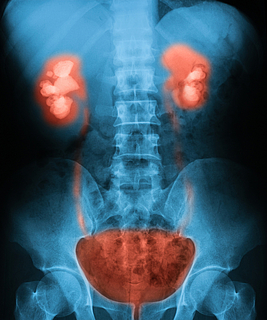

- communes aux deux sexes : reins, uretères, vessie, urètre

Calculs rénaux et vésicaux

Les calculs rénaux ou lithiase urinaire sont des cristaux solides qui se forment

dans les reins. Ceux-ci peuvent ensuite migrer dans le reste de l’appareil urinaire,

soit dans l’uretère, la vessie ou l’urètre et provoquer de fortes douleurs que l’on

appelle colique néphrétique.

Cancer des organes du système urogénital

Ce terme désigne les organes urinaires et génitaux chez l’homme et la femme. Diverses

problématiques peuvent les concerner, notamment le cancer au niveau de la vessie et du rein ainsi que des testicules chez l’homme.